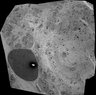

Scanning transmission electron microscopy of Islets of Langerhans.

Study Type: electron microscopy volume map

Imaging Method: scanning-transmission electron microscopy